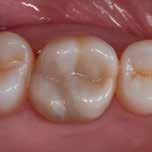

Fig. 5: Intraoral image taken with the Cam interchangeable head of VistaCam iX HD Smart to visualise an occlusal caries lesion. (Image: Practice Dr. Frank Döpper)

Fig. 6: Caries detection with the VistaCam Proof interchangeable head. The left of the image shows the representation in the caries filter with different colours used to highlight the development of the caries, while the right shows the numerical values for the caries activity. (Left-hand image: Practice Dr. Frank Döpper; right-hand image: Dürr Dental)